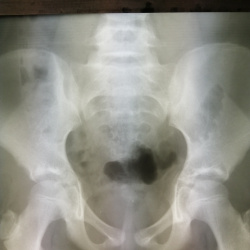

Коллеги, здравствуйте! Женщина, 83, жалобы на боли в тазобедренном суставе. На прямом снимке меня смутил обведенный оранжевым экзостоз. Было не понятно, что это и где, доделали снимок с отведением. А...